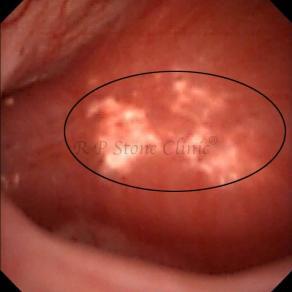

Kidney stone is a solid mass of CRYSTALS. It is the process of crystallization which initiates the formation of kidney stones. This happens in nephrons or units of kidney. Once a small crystal is formed, it can both grow & unite with other crystals leading to the formation of small concretion which eventually forms a stone. Once these large crystals detach from the collecting ducts, the process of stone formation starts in the renal collecting system. A recurrent kidney stone former is advised to know a little bit about something known as Randall’s plaque. Alexander Randall discovered plaques on the renal papillae eight decades back based on examination of 1154 pairs of autopsied Kidneys. He described these renal papillary lesions as cream colored or milk patch areas composed of calcium phosphate & calcium carbonate. These plaques could act as NIDUS for formation of KIDNEY STONE. Calcium Oxalate stone can form on this nidus & then detaches from this plaque to become a free floating stone in the collecting system of kidney

These images are taken as snap shots from the video recording of RIRS Surgery done at our hospital. These are Randall’s Plaques seen with Digital FLEX XC & Digital FLEX XC S. The cream or whitish patches are seen on the tips of RENAL PAPILLAE as seen in images below.

Randall’s Plaques may lead to the formation of Stones.

Those kidney stone patients who have Randall’s Plaques in their kidneys are more likely to form stones again (Recurrent Stones).